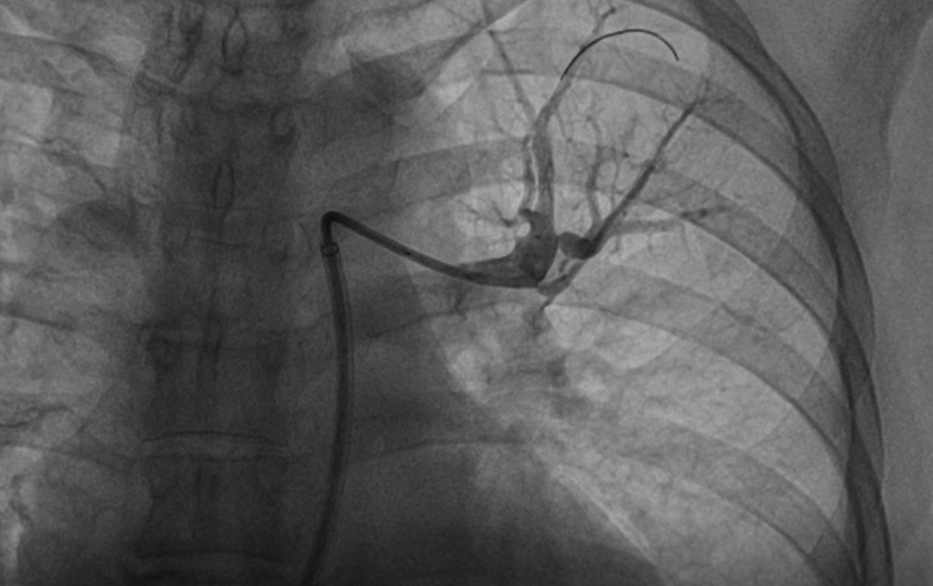

患者慕名至我院后,我科专家进一步对其进行了相关检查,最终诊断为:慢性血栓栓塞性肺动脉高压。心内科周亚峰副院长、陈弹主任、赵良平主任及团队成员进行深入讨论,并邀请呼吸科、血管外科与介入科等进行多学科(MDT)会诊,最终决定对其进行右心导管及肺动脉造影检查,结果提示肺动脉收缩压52mmHg,平均肺动脉压33mmHg,左右各肺动脉及其分支多发栓塞,可见多处血栓影及马赛克征。对右肺动脉A3、左肺动脉A1+2、左肺动脉A9行球囊扩张术,扩张后复查造影远端血流恢复良好。手术后患者的症状得到明显改善,心功能逐渐恢复,住院5天后平稳出院。出院后患者继续进行家庭氧疗、抗凝、利奥西呱降肺动脉压力等治疗,并密切随访中。随访至今,患者情况良好。

左肺动脉A1+2扩张前